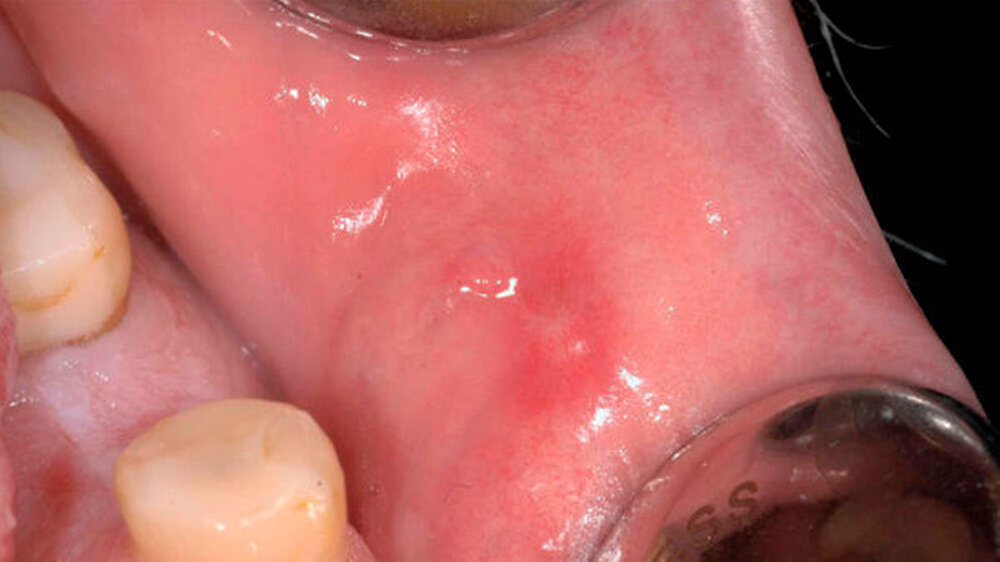

Ein 49 Jahre alter Patient wurde der Klinik zur Abklärung einer seit fünf Jahren persistierenden Mundschleimhautveränderung zugewiesen. Der Mann war zum Zeitpunkt der Erstuntersuchung beschwerdefrei, hatte aber seit zwei Jahren eine kontinuierliche Größenzunahme der Läsion beobachtet. Klinisch präsentierte sich eine runde, gestielte, weiche, verschiebliche, 9×9 mm große, gut durchblutete Veränderung mit einem zentralen Ulkus an der bukkalen Mukosa regio 35 (Abbildung 1).